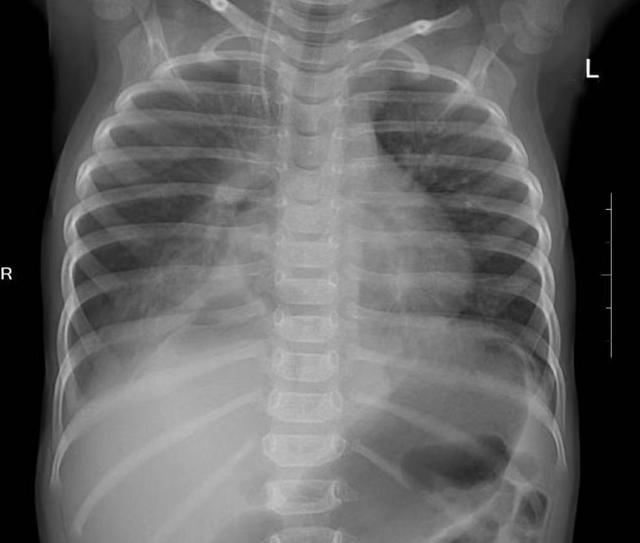

(▲术后)

手术效果立竿见影。术后第一天,依依开始进食,困扰她一个多月的呕吐消失了。术后第三天复查,受压的右肺已完全张开。术后一周,依依顺利康复出院。